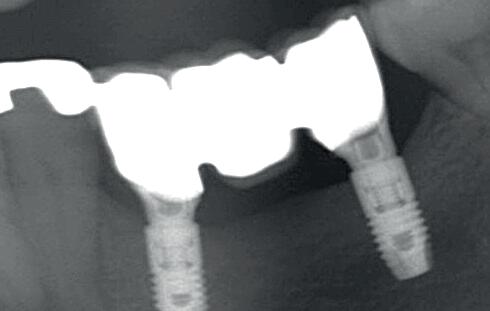

Bij klinisch en röntgenologisch onderzoek viel echter op dat radix van de 12 en 22 een convergerende (de radices staan dan naar mesiaal en naar elkaar toe) in plaats van divergerende (radices staan dan van elkaar af) stand had. Door deze convergerende stand van de radices was er in mesio-distale zin geen ruimte voor twee implantaten ter plaatse van de 11 en 21. Er werd daarom besloten, in tegenzin

1. Retainer met twee frontelementen

2. OPT radices 12 en 22 convergeren

4. OPT radices 12 en 22 divergeren na orthodontische behandeling

van de patiënt, om eerst weer vaste apparatuur terug te plaatsen om de radices in een divergerende stand te plaatsen. Gelukkig verliep deze behandeling voorspoedig. (afbeelding 2 -4). Het volgende behandelplan werd gemaakt: